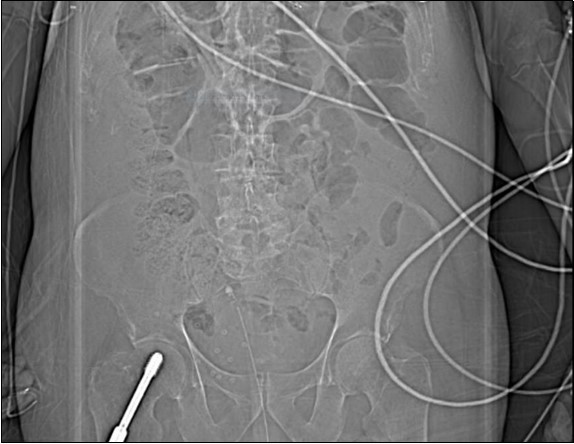

His irrigation circuit-chart showed he had received 10 litres Normal Saline via the afferent limb, but only 3 litres recorded at the efferent limb. It was suspected the catheter was adjacent to a vascular-cystic interface, however an urgent contrast CT revealed the irrigating catheter perforating the bladder, being situated in the abdominal cavity (see 3 images). His arterial blood-gas analysis demonstrated the expected normal anion-gap academia, however his Strong Ion Difference calculations, sodium-chloride difference of 13 and a normal albumin level, perfectly demonstrated the expected calculated BE of -13. The catheter was withdrawn, and the patient made a full recovery.

An urgent CT abdomen revealed a bladder perforation with the tip of the irrigating catheter situated in the abdominal cavity (Figure 1, Figure 2, Figure 3a,Figure 3b). This was most likely due to over-insertion of the 3-way catheter due to the extra force required because of the benign prostatic hypertrophy. He had therefore been receiving normal saline as ‘peritoneal dialysis’ with normal saline since insertion of the catheter. The catheter was withdrawn, and the patient made a full recovery.

Figure 1.coronal plane CT scout image